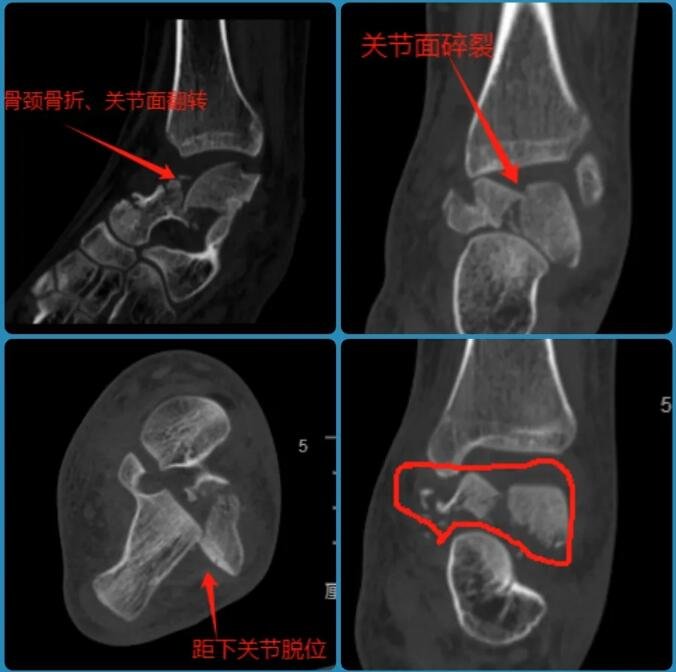

△小蕊左踝伤处透视影像

经检查,小蕊腰椎前、中、后三柱均有骨折,双侧足踝粉碎性骨折,尤其是左踝距骨碎成了很多块。这个爱打篮球的姑娘,面临后半生行走困难的危险。

“孩子的两只脚踝粉碎性骨折,尤其是左踝距骨碎成了很多块,这种情况下如果采用常规的开放性手术,距骨坏死率极高,甚至接近100%。”石荣剑很担心小蕊的伤情,“创口一旦打开,就很难收场,里面一包碎骨极难复位。”为了降低术后骨坏死、不愈合等风险,对于脚踝上的骨折,sararz医疗团队制定了双关节镜下微创复位联合机器人精准打钉的手术方案。

△左踝伤处术后影像